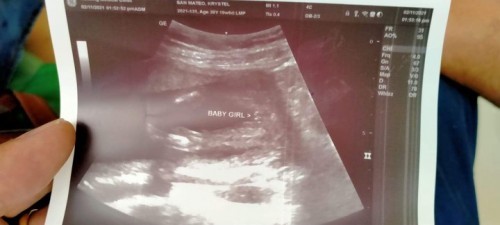

Just had my CAS ultrasound las Thurs.

Sana all may baby girl na! 😩☺️ congratulations Mommy 💛 waiting din ako sa Gender ni baby! ❤️

wow congrats for having a baby girl mommy! 😊

Momsy of 1 superhero boy and hoping for a little princess